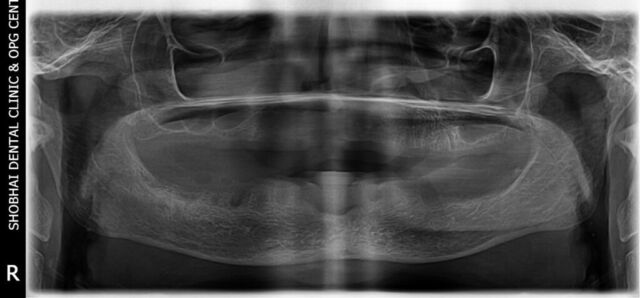

It’s a 500 square feet spacious dental setup located in a prime location in Kalyan west. The Clinic has in house OPG machine for early diagnosis and latest sterilization equipment. Our team is very well trained for handling all types of dental treatments and emergencies.

We offer all types of dental treatments at our dental clinic including basic and advanced treatments like full mouth dental implants.